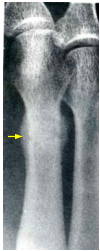

27 35 歲男性登山客抱怨足痛兩週多,醫師開立 X 光檢查如圖所示,其最可能之診斷為何?

(A)鈣化性肌炎 (B)類風濕性關節炎 (C)骨腫瘤 (D)行軍骨折